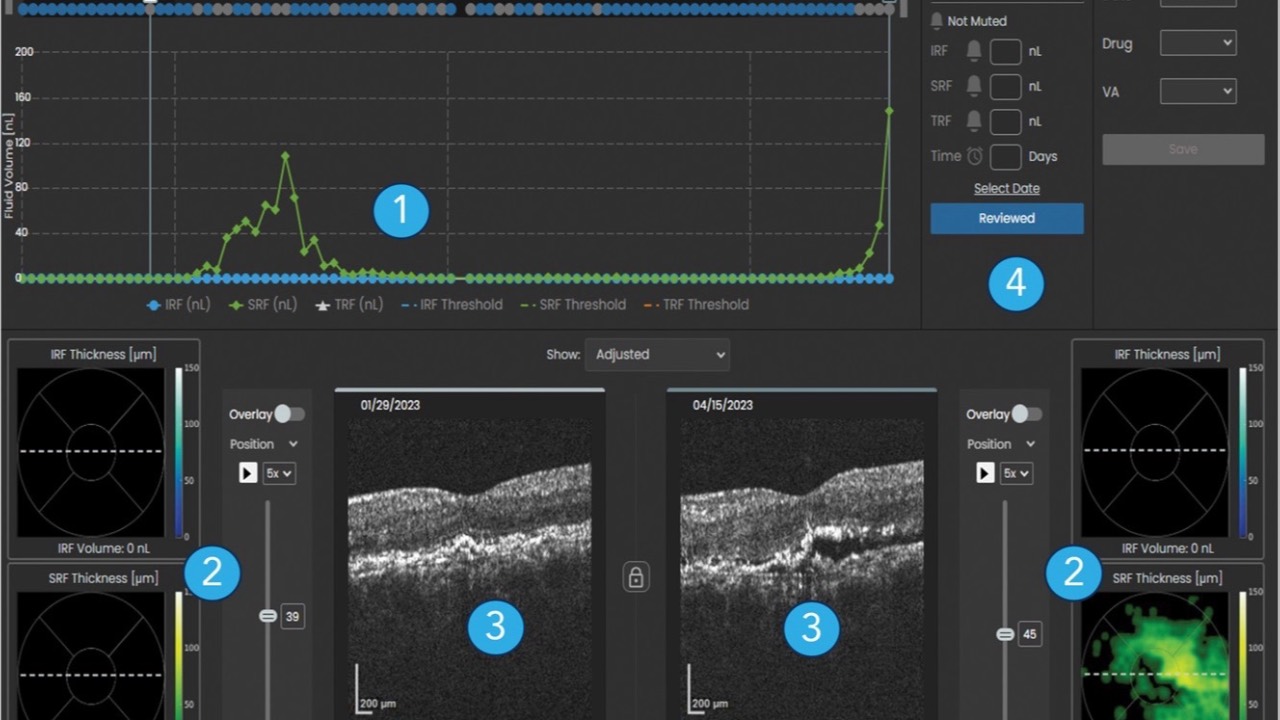

Home OCT?

Is this the future?...

A recent prospective trial published in Retina investigating home optical coherence tomography (OCT)-guided management of neovascular age-related macular degeneration (nAMD) has yielded promising results.

The study, involving 15 patients over 6 months, demonstrated a sig...